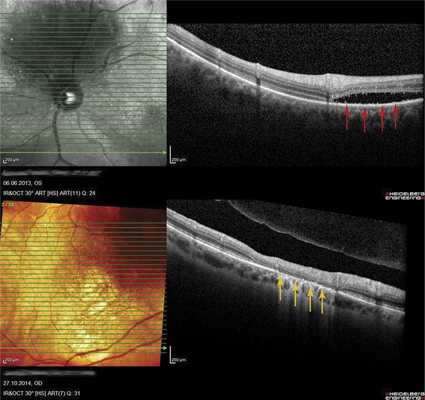

В 8 случаях выявили распространенную зону ОНЭ с дезорганизацией фоторецепторного слоя «на протяжении» от очага (рис. 6, а). В 2 случаях при анамнезе более 15 лет были выявлены зоны разрушения слоя фоторецепторов и наружных слоев сетчатки, соответствующие зонам ранее существовавшей ОНЭ (см. рис. 6, б).

Рис. 6. ОКТ-горизонтальный срез «на протяжении» от ГХ. а - пациентки Х., длительность анамнеза 3,5 года (красными стрелками указана зона ОНЭ); б - пациентки К., длительность анамнеза 15 лет (желтыми стрелками указана зона разрушения слоя фоторецепторов и наружных слоев сетчатки на месте ранее существовавшей ОНЭ, атрофия РПЭ).

Как показывают наши наблюдения, ГХ может быть подвержена саморегрессии. Мы имели возможность наблюдать больную 66 лет, у которой в 2005 г. была выявлена ГХ проминенцией 5,5 мм (рис. 7, а). Больная отказалась от лечения и находилась под наблюдением. При контрольном исследовании спустя 9 лет по данным ОКТ и УЗИ отмечено уменьшение толщины ГХ до 1,2 мм (см. рис. 7, б-г). Очаг, по данным ОКТ, «выстоял» в сторону склеры, куполообразная проминенция в сторону сетчатки отсутствовала. Аналогичный случай описан M. Munteanu и соавт. в 2013 г. [17].

Рис. 7. Офтальмоскопическая картина глазного дна при саморегрессии ГХ (в) и соответствующие данные УЗИ в динамике (а - на момент выявления ГХ; б - при контрольном обследовании через 9 лет) и результат ОКТ (г) (красными стрелками отмечена область изменений в хориоидее, желтыми - в сетчатке).